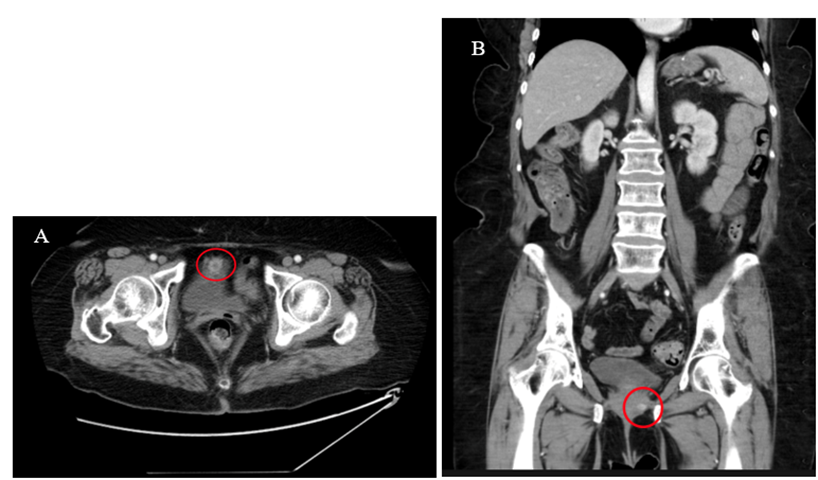

A 69-year-old female presented to our institution with an approximately 8-month history of intermittent sharp lower abdominal pain. She also complained of irritative voiding symptoms and her urinalysis was significant for microscopic hematuria. She had previously undergone an unknown ‘bladder tacking’ surgery in the early 1990s. Additional significant surgical history included a total abdominal hysterectomy in 1994, a sacrospinous ligament fixation for Pelvic Organ Prolapse (POP) in 2018, followed by a repeat sacrospinous ligament fixation for recurrent POP in 2019, and finally a laparoscopic sacrocolpopexy for a second recurrence of her POP. Cystoscopy performed at the time of her 2022 surgery was reportedly normal. A contrast Computed Tomography (CT) scan of the abdomen and pelvis was obtained which showed an enhancing mass involving the anterior aspect of the urinary bladder and was read as either a primary urinary bladder neoplastic process or lesion associated with the urachal ligament (Figure 1).

Figure 1: Axial (A) and coronal (B) contrast-enhanced CT images of the abdomen and pelvis demonstrating an enhancing mass along the anterior aspect of the urinary bladder.